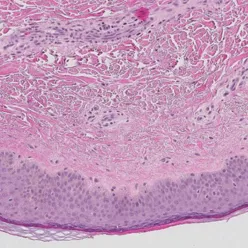

Livmorhalskreft

- "Who are at risk of developing cervical cancer?" Utvikling av nye biomarkører som kan forutsi hvilke kvinner som har risiko for å utvikle livmorhalskreft. Fokus på immunforsvar og genetiske endringer i vevet. Samarbeidsprosjekt med Kreftregisteret og Sørlandet sykehus.